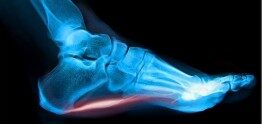

It is the most commonly occurring cause of heel pain, involving a band of tissue in the foot called the plantar fascia that connects your heel bone to your toes. It’s job – to help support the arch in your foot during your normal walking and running gait. Injury to this tissue can occur for a wide variety of reasons but usually affects the area just in front of the heel bone. And the pain can be the most sore in the morning, after rest or when pressed directly. During the early stages, plantar fasciitis pain tends to ease off with activity, but as time goes on the pain may not subside entirely.

There are thought to be a few possible causes of plantar fasciitis. The most widely recognised is by mechanical stress either by abnormal motion of the heel itself, excessive load/impact or by a traction injury where the plantar fascia is being pulled too much. The second is due to the development of heel spurs causing fibrosis and calcification and weakness in the plantar fascia and the final possible cause is by an inflammatory joint disease like arthritis.